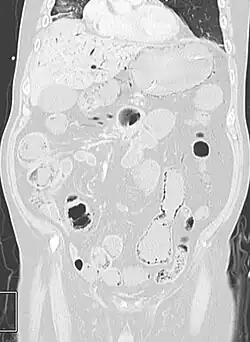

Pneumatosis intestinalis (also called intestinal pneumatosis, pneumatosis cystoides intestinalis, pneumatosis coli, or intramural bowel gas) is pneumatosis of an intestine, that is, gas cysts in the bowel wall.[1][2] As a radiological sign it is highly suggestive for necrotizing enterocolitis. This is in contrast to gas in the intestinal lumen (which is relieved by flatulence). In newborns, pneumatosis intestinalis is considered diagnostic for necrotizing enterocolitis, and the gas is produced by bacteria in the bowel wall.[3] The pathogenesis of pneumatosis intestinalis is poorly understood and is likely multifactorial. PI itself is not a disease, but rather a clinical sign. In some cases, PI is an incidental finding, whereas in others, it portends a life-threatening intra-abdominal condition.